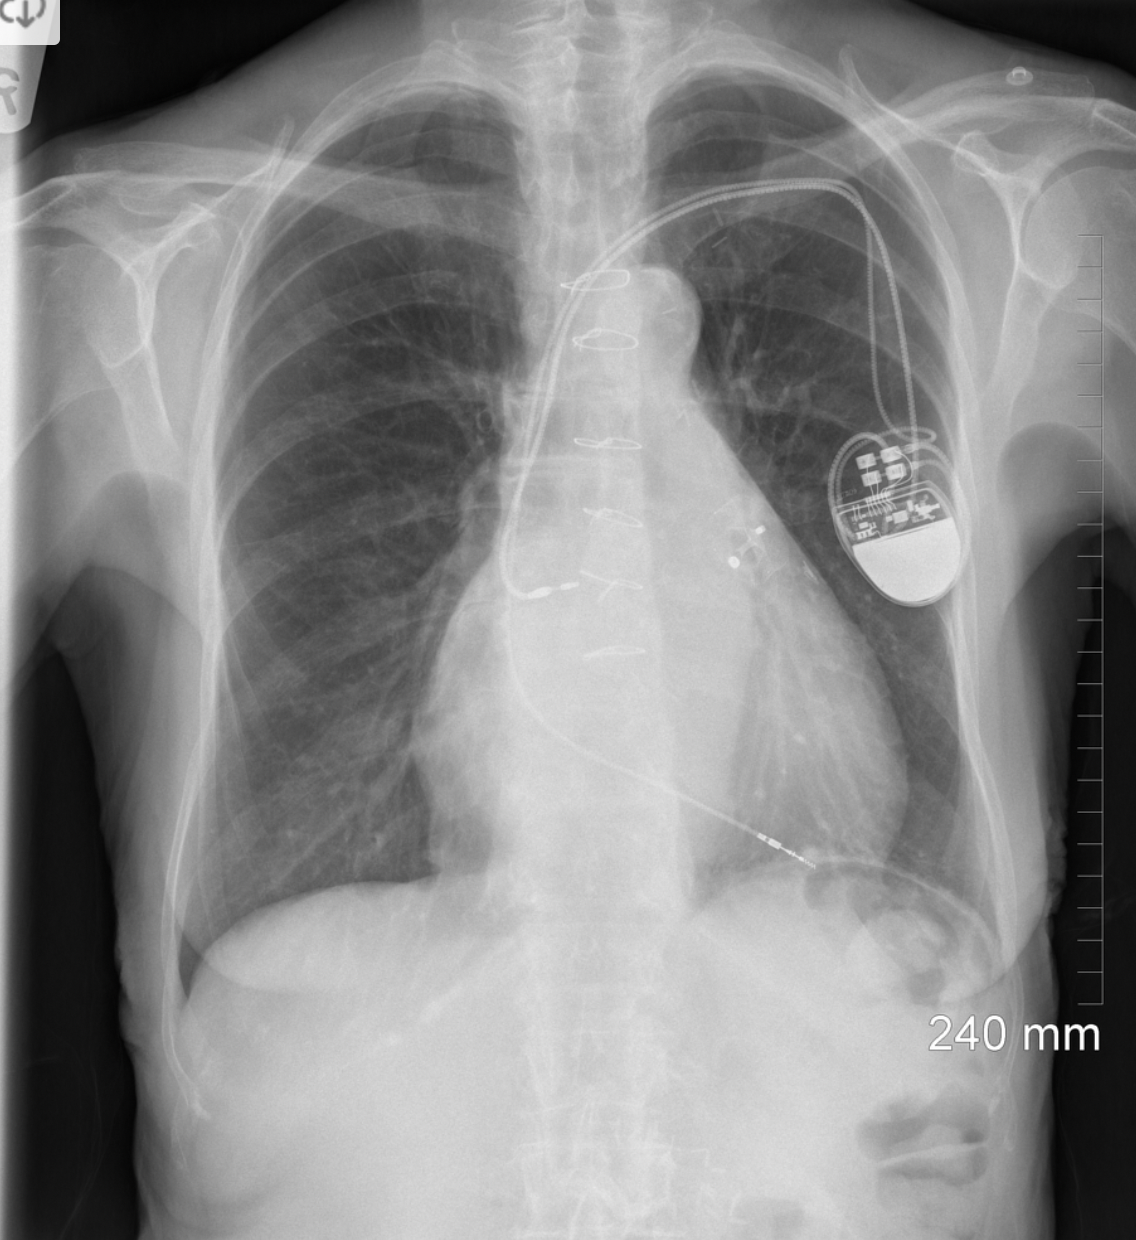

8

Q

A

-LAA Occluder device

-Sternotomy clips

-Dual chamber pacemaker

How well did you know this?